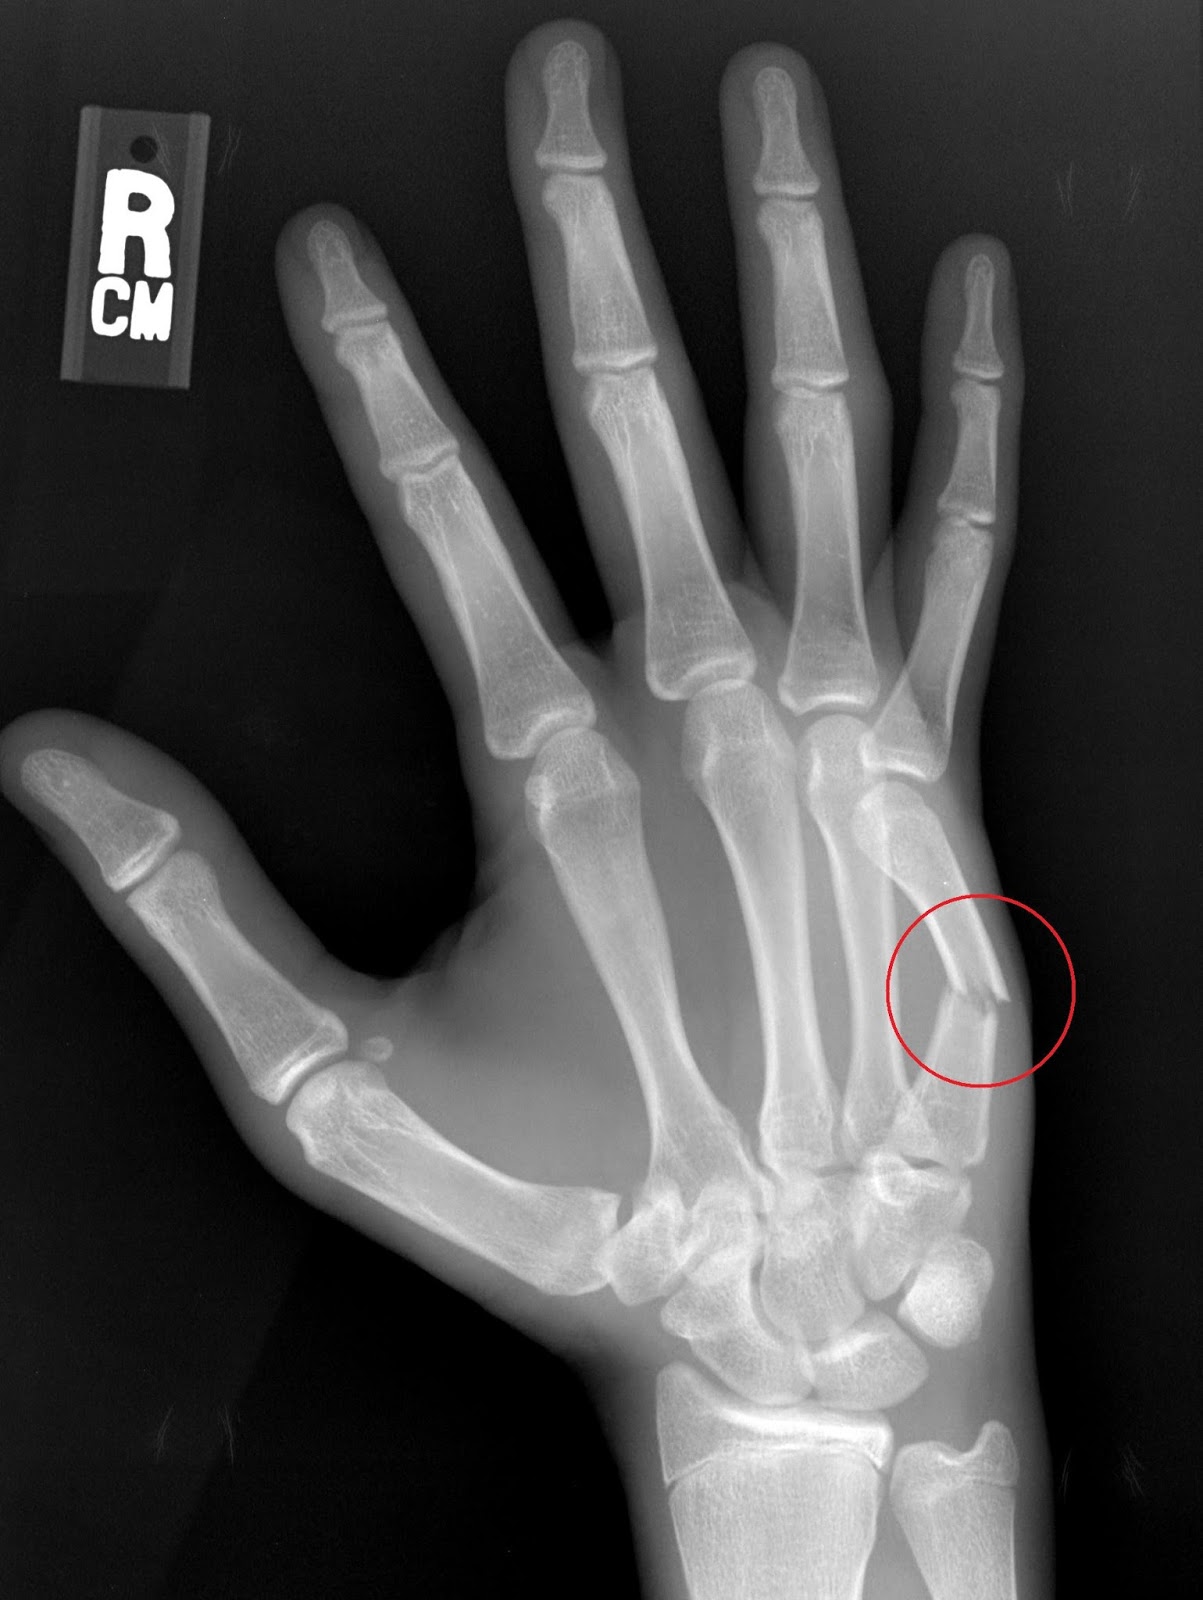

Boxing Wrist Fracture . A boxer's fracture is a break in a metacarpal bone that connects the ring finger or the little finger to the wrist. A boxer's fracture occurs when the neck of the fifth metacarpal bone breaks, usually resulting from a direct blow with a clenched fist. That bone is known as a metacarpal. The fracture of the fifth metacarpal neck also known as boxers fracture, named after the classic mechanism of injury in which direct trauma is. A boxer's fracture, or metacarpal fracture, is a bone fracture that affects knuckles in the hand. These are known as the fourth and fifth. Causes include punching or smacking with the hand, or dropping something on the hand. A boxer’s fracture is when you break a bone at the base of your finger, near the knuckle or neck of the bone. A boxer’s fracture may also be called fifth.

Boxer fractures are minimally comminuted, transverse fractures of the Boxing Wrist Fracture A boxer’s fracture is when you break a bone at the base of your finger, near the knuckle or neck of the bone. That bone is known as a metacarpal. A boxer's fracture occurs when the neck of the fifth metacarpal bone breaks, usually resulting from a direct blow with a clenched fist. A boxer’s fracture may also be called. Boxing Wrist Fracture.

Clinical Cases and Images Boxer's Fracture Boxing Wrist Fracture A boxer's fracture is a break in a metacarpal bone that connects the ring finger or the little finger to the wrist. These are known as the fourth and fifth. A boxer's fracture occurs when the neck of the fifth metacarpal bone breaks, usually resulting from a direct blow with a clenched fist. The fracture of the fifth metacarpal neck. Boxing Wrist Fracture.

Punchin’ out Fifth metacarpal (boxer’s) fracture Radiology Key Boxing Wrist Fracture These are known as the fourth and fifth. The fracture of the fifth metacarpal neck also known as boxers fracture, named after the classic mechanism of injury in which direct trauma is. A boxer's fracture is a break in a metacarpal bone that connects the ring finger or the little finger to the wrist. A boxer’s fracture is when you. Boxing Wrist Fracture.

Boxer's fracture Radiology at St. Vincent's University Hospital Boxing Wrist Fracture A boxer's fracture occurs when the neck of the fifth metacarpal bone breaks, usually resulting from a direct blow with a clenched fist. A boxer’s fracture is when you break a bone at the base of your finger, near the knuckle or neck of the bone. A boxer’s fracture may also be called fifth. A boxer's fracture is a break. Boxing Wrist Fracture.